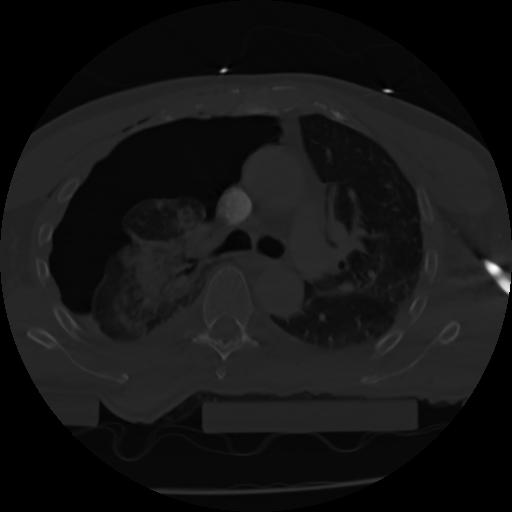

21 ANGIO,CE,Axial,3.0,ANGIO,,